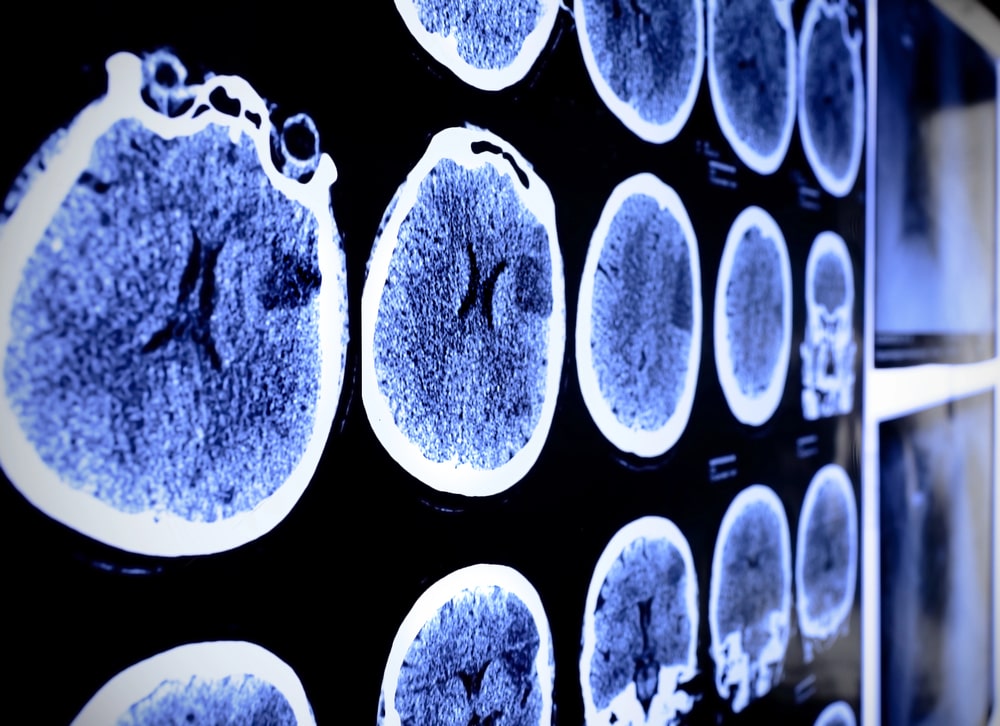

A Magic Mountain theme park in California is seeking to dismiss a lawsuit stemming from an alleged brain injury caused by its X2 roller coaster. The plaintiff—a 53-year-old woman—claims that the ride led to a serious neurological injury during a visit to the park in 2020, resulting in significant medical expenses and an inability to…